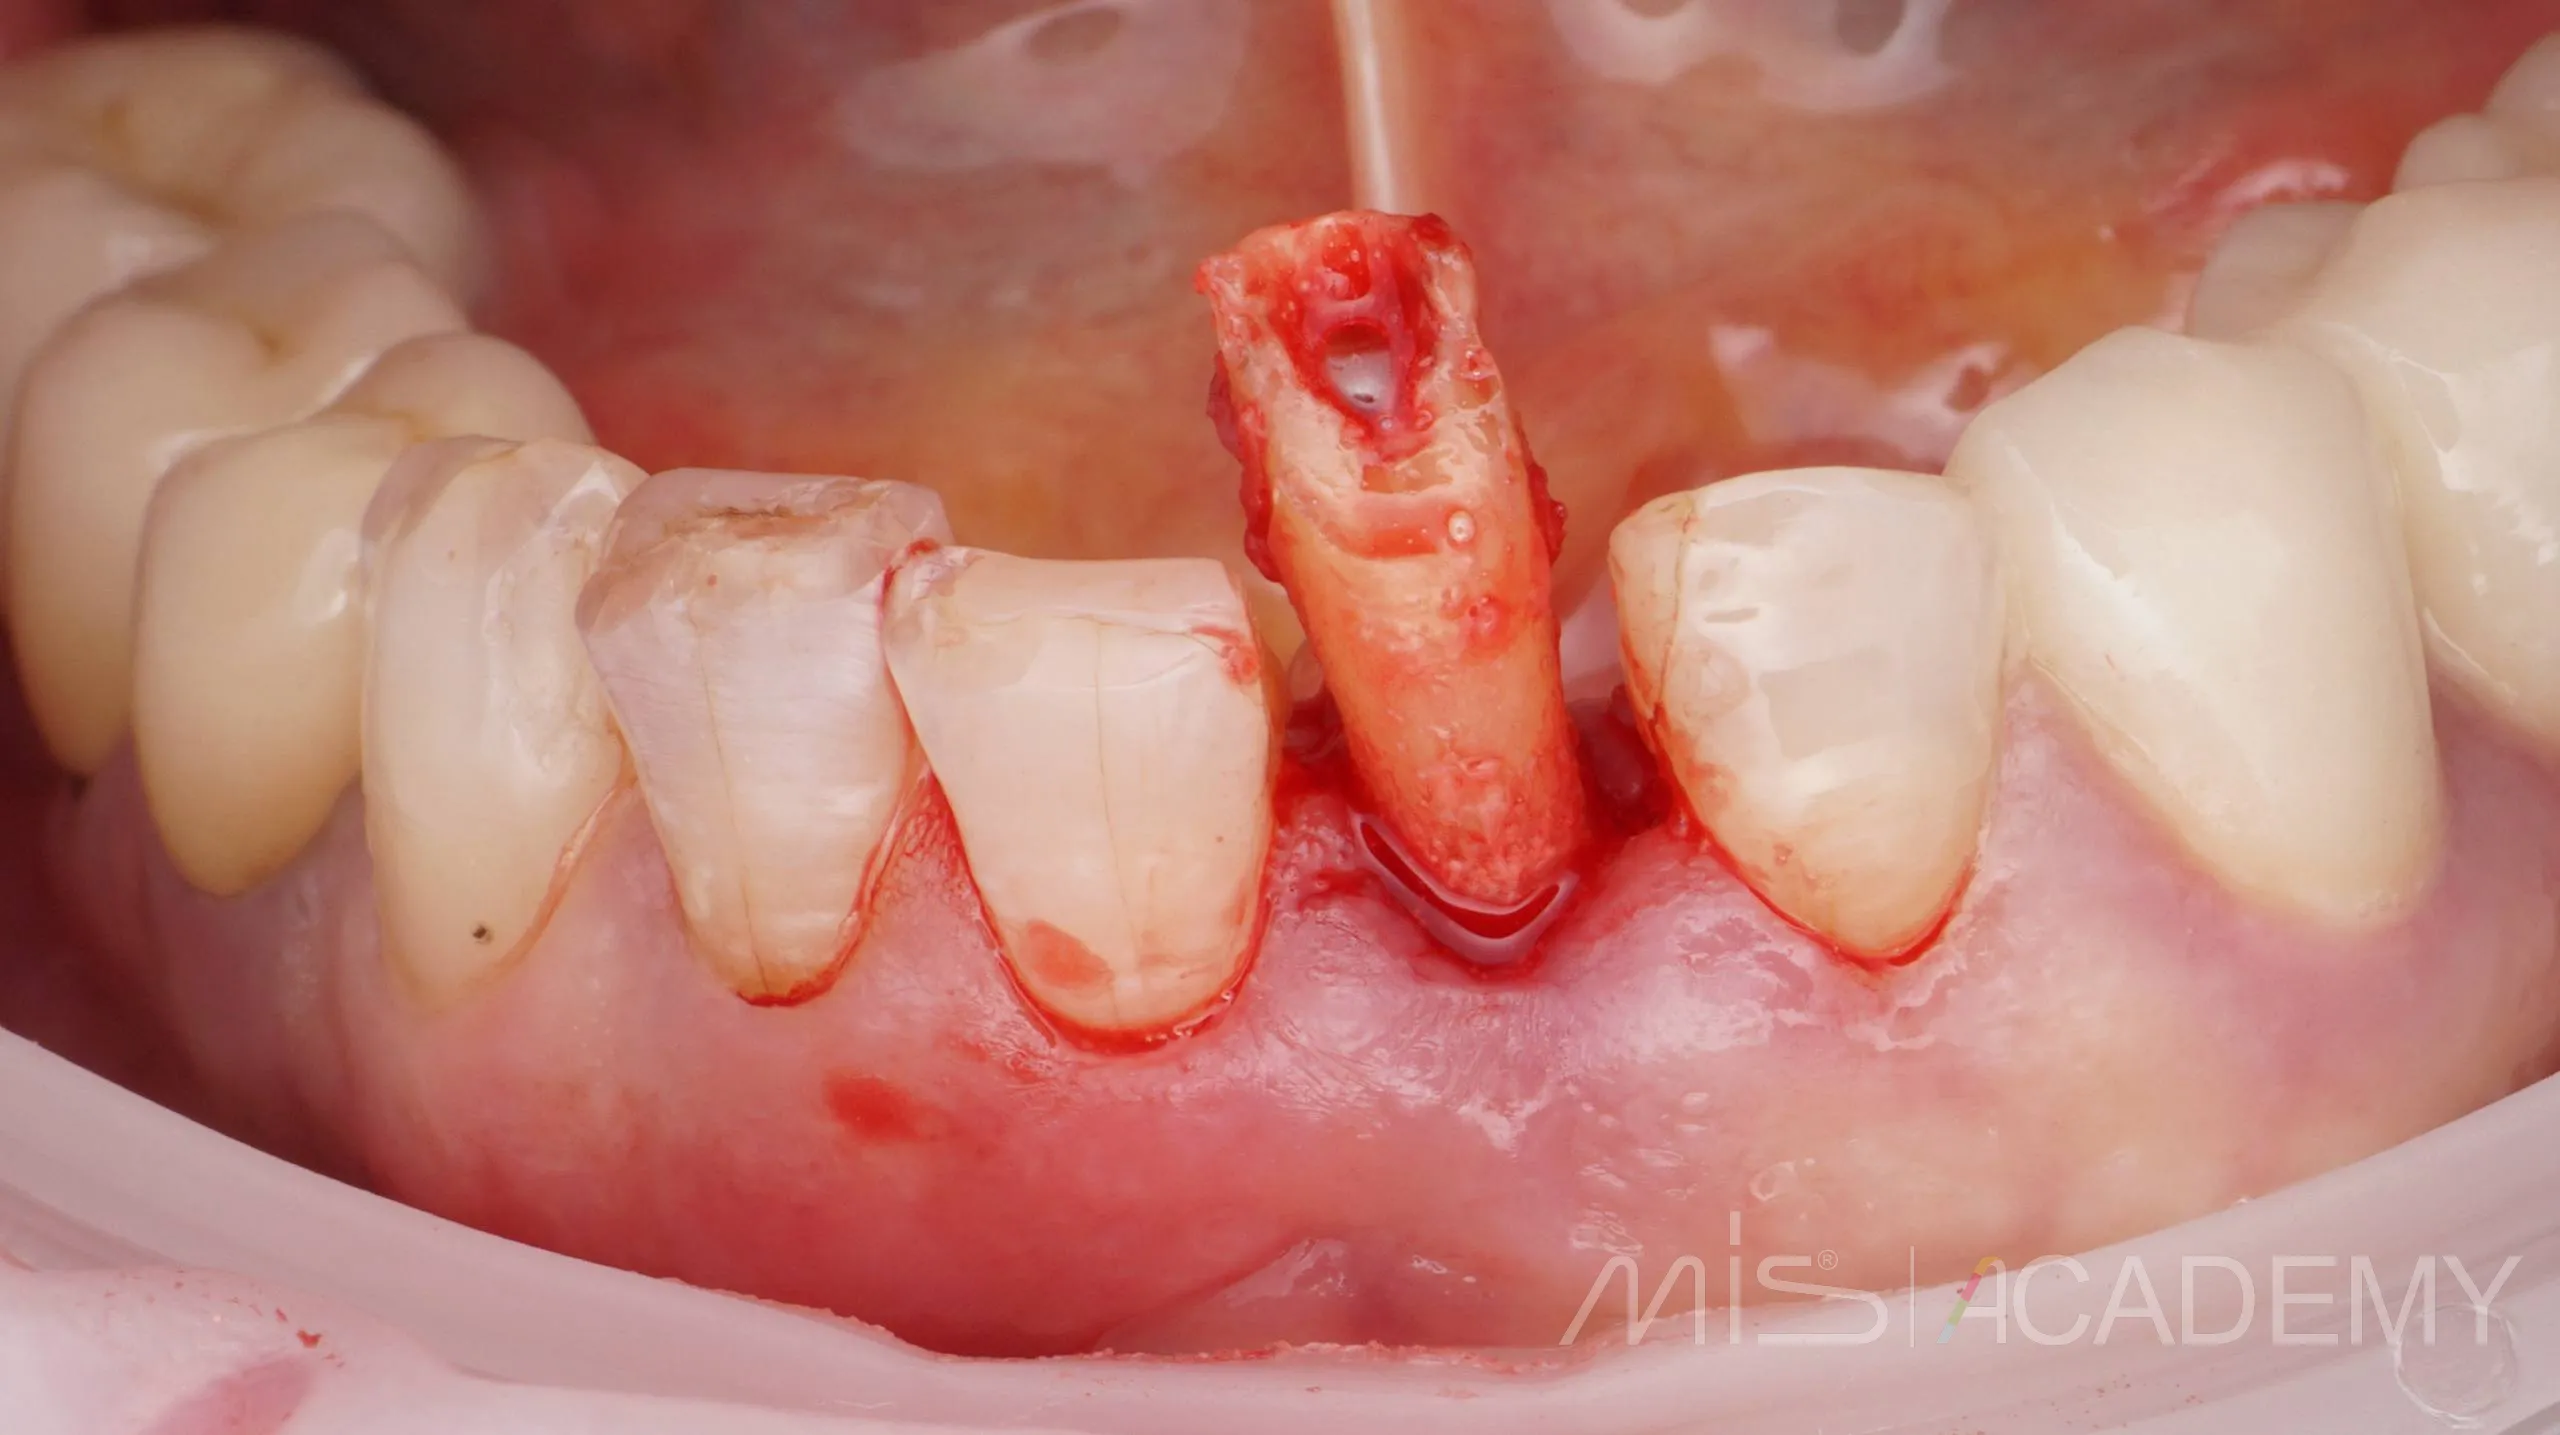

Одномоментная имплантация MIS С1